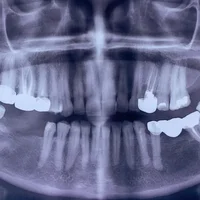

Défauts osseux autour des dents

Défauts de l'alignement dentaire

Complications après un traitement endodontique